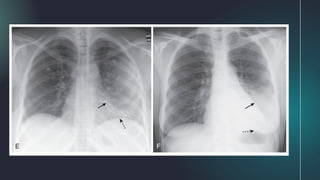

3. Lower Lobe Atelectasis

A. Frontal radiograph:

● both right and left lower lobes collapse to

form a triangular density (Fig. A)

● downward shift of major fissure (Fig. C)

● shift of the heart towards the atelectasis

● elevation of the hemidiaphragm on the

affected side

B. Lateral radiograph:

● both downward and posterior displacement

of the major fissure (Fig. B)

○ until the completely collapsed lower

lobe forms a small triangular density

at the posterior costophrenic angle

● In the critically ill patient, atelectasis occurs most frequently in the left lower lobe

○ Always check the left hemidiaphragm to be sure it is seen in its entire extent through the heart

shadow

■ left lower lobe atelectasis will manifest by disappearance (silhouetting) of all or part of the left

hemidiaphragm (Fig. C)